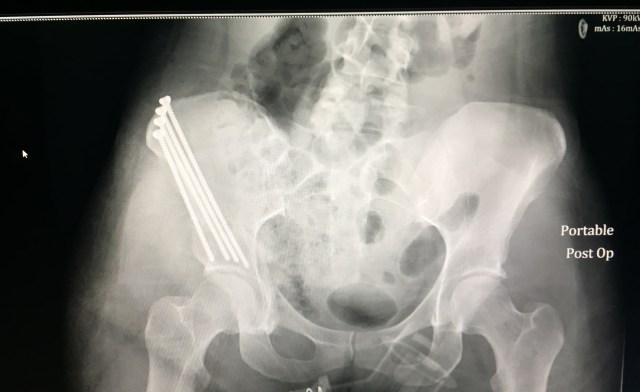

Here are some fun photos of my shark fin and my new hardware (graphic warning, don’t say I didn’t try!):